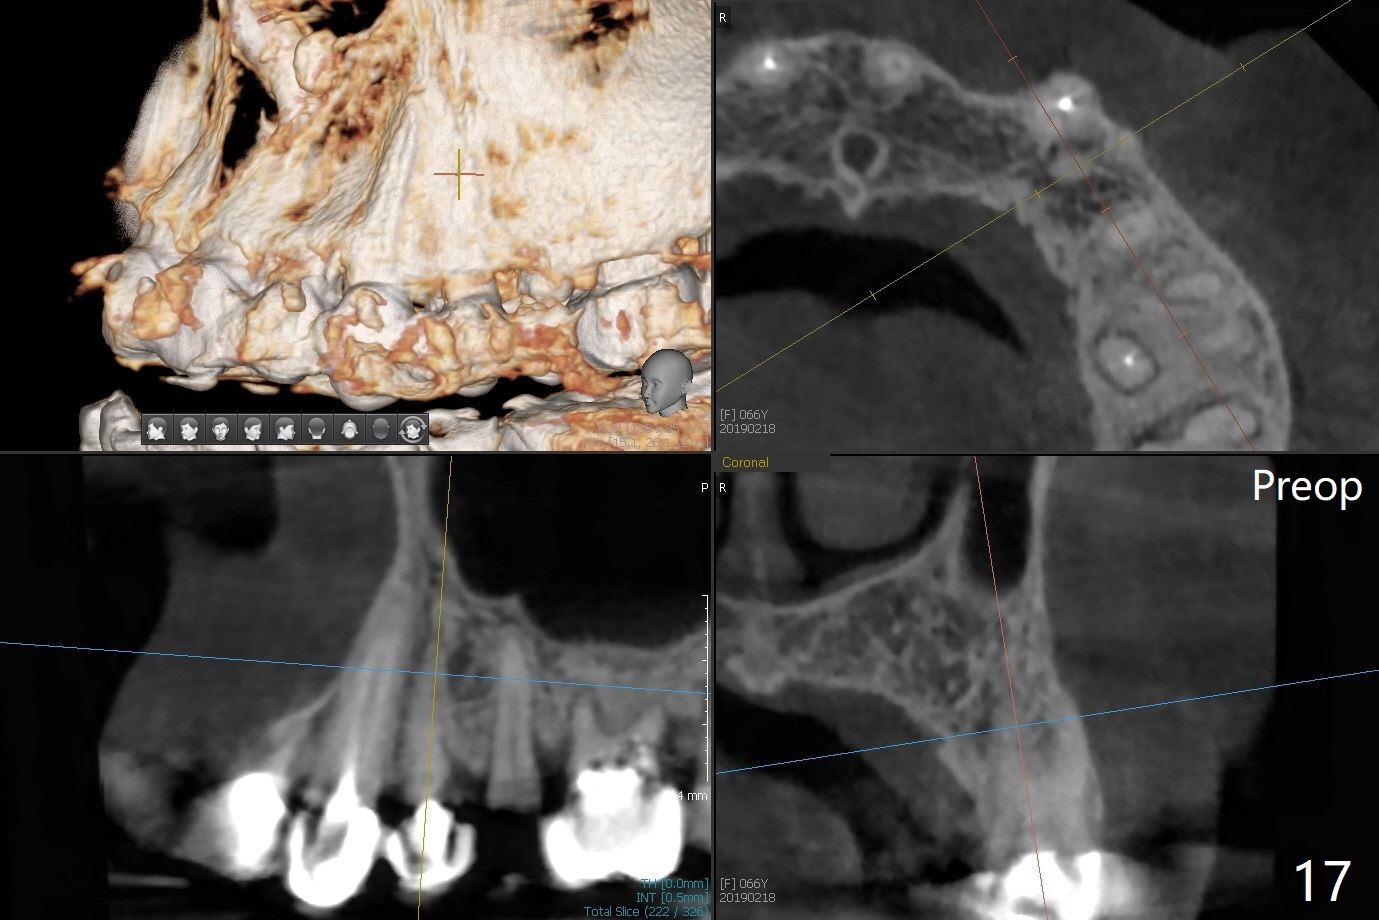

68岁女左上4颊侧瘘道(图一:*),与根尖颊侧骨板缺失相通,其实腭侧根尖周围病变更大(也与颊侧窝相通),术中没有注意腭侧根接近3(图二:P),稀里糊涂的基本顺着腭侧根(颊侧)走向钻洞(图四,与图三理想方向对比),突然记起术前设计钻洞必须在腭侧牙槽窝远中颊侧,在远中建立新洞眼(图五),之后无法再次建立新洞眼,只好利用同一个侧面切割钻头将钻洞往远中移位,同样效果不佳(图六),最后只好放弃,放置粘性骨粉(图七:*),覆盖PRF膜,6个月胶原膜,PGA缝线,牙周胶水。术后重新分析表明顺着腭侧牙槽窝种植与尖牙还是有分离(图八,九:*),因为牙槽窝是斜型的(图十:黑色),不过离颊侧骨板也接近(图八:B)。所以钻洞必须斜型针对远中骨壁,表浅些(图十一:红色箭头);一旦进入骨板,改变角度(图十二:红色箭头),适当矫枉过正,随着植体增大,钻洞会往近中偏移(白色箭头)。最好植体方向理想(图十三)。不过植骨后钻洞偏移可能性比较少。缝线和牙周胶水似乎是一个稳妥固定胶原膜方法。术后病人抱怨水肿严重,术后八天颊侧根尖隆起是由于骨粉推出骨板之外(图十五,十六:*),上颌窦底板无意穿孔(^)伴有上颌窦膜(M)增厚,与术前对比(图十七:上颌窦窦腔清晰)。术后一个月6个月吸收膜不见了,大多数缝线已经脱落,最后两根缝线撤除后,牙槽窝开口已经关闭,好像主要成分是骨粉(图十八)。术后5个月牙槽嵴宽,角化龈也宽,好像可以植入4x11.5毫米植体(图十九)。